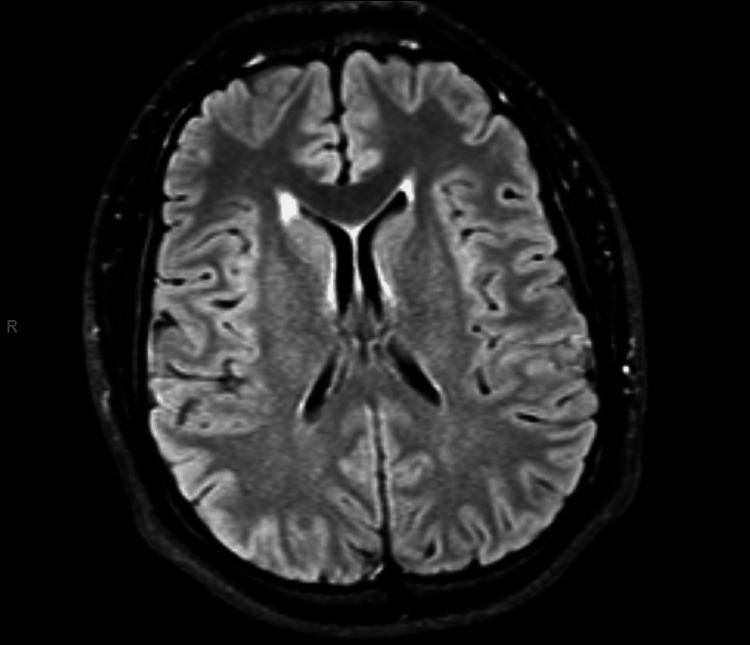

This case highlights a rare instance of alcohol-induced neuroleptic malignant syndrome (NMS) complicated by acute severe rhabdomyolysis, emphasizing the importance of recognizing atypical presentations of NMS. In June 2024, a 22-year-old male presented to the emergency department of a tertiary hospital in Florida with an acute alteration in mental status following alcohol consumption. Physical examination revealed neurological deficits alongside significant vital signs, including a temperature of 38°C, tachycardia, and hypertension. Key laboratory findings included a creatinine phosphokinase (CPK) level exceeding 100,000 U/L, aspartate aminotransferase (AST) above 3,000 U/L, alanine aminotransferase (ALT) above 500 U/L, and a lithium level below 0.20 mmol/L. The patient's medical history of bipolar disorder, managed with lithium, and recent alcohol intake suggest alcohol's role as a trigger for NMS in the context of lithium treatment, compounded by severe rhabdomyolysis. This case underscores the need for heightened clinical awareness of such complex interactions and highlights the critical importance of early recognition and multidisciplinary management to prevent potentially fatal complications.

该病例突出了酒精诱发的神经阻滞剂恶性综合征(NMS)并发急性严重横纹肌溶解这一罕见情况,强调了认识NMS非典型表现的重要性。2024年6月,一名22岁男性因饮酒后出现急性精神状态改变,就诊于佛罗里达州一家三级医院的急诊科。体格检查发现神经功能缺损以及显著的生命体征异常,包括体温38°C、心动过速和高血压。关键实验室检查结果包括肌酸磷酸激酶(CPK)水平超过100,000 U/L、天冬氨酸转氨酶(AST)高于3,000 U/L、丙氨酸转氨酶(ALT)高于500 U/L以及锂水平低于0.20 mmol/L。患者有使用锂治疗双相情感障碍的病史且近期饮酒,提示在锂治疗背景下酒精是诱发NMS的因素,并伴有严重横纹肌溶解。该病例强调了对此类复杂相互作用提高临床认识的必要性,并突出了早期识别和多学科管理对预防潜在致命并发症的至关重要性。